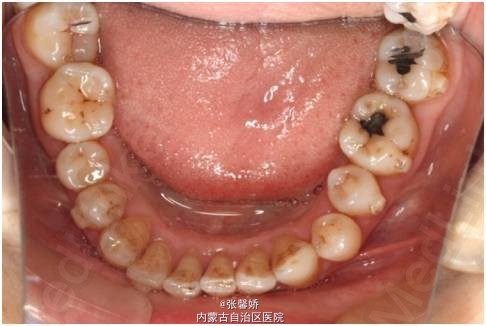

查体 辅查

上中线右偏1mm,A2、D4反合,A2、B2畸形牙偏小,拥挤度上颌4mm、下颌6mm。Spee曲线:左侧3mm,右侧2.5mm